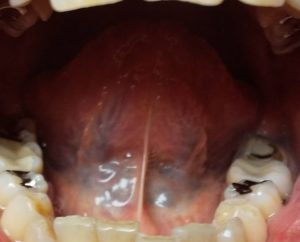

【2021年2月18日漢方薬服用前舌裏】

【2021年3月11日漢方薬16日分服用中舌裏】